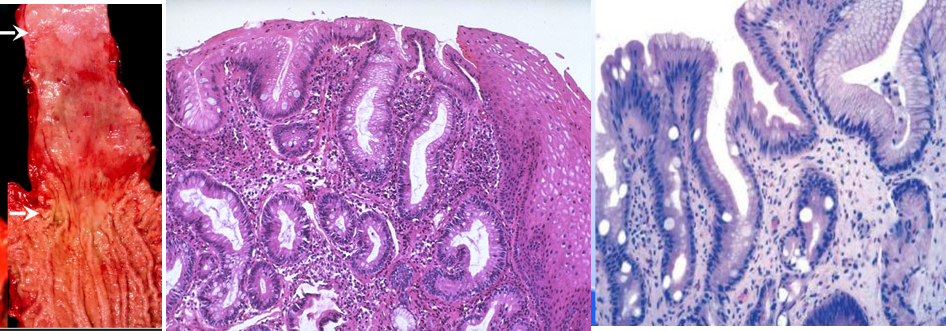

4.Barrett食管(barrett’s esophagus) 长期的胃-食管返流,食道鳞状上皮被柱状上皮取代。有人称之为胃贲门粘膜上移,也有人称之为化生。常出现在食管—贲门粘膜上皮齿状交界线3cm以上的粘膜。柱状上皮为贲门粘膜上皮或胃底粘膜上皮,常伴不完全性肠上皮化生。现认为其是一种癌前病变,可恶性转化,发生腺癌。